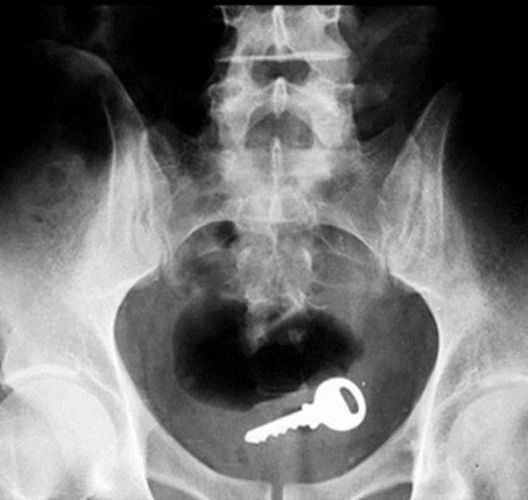

Os objetos mais BIZARROS encontrados no ânus pelos médicos

Chave